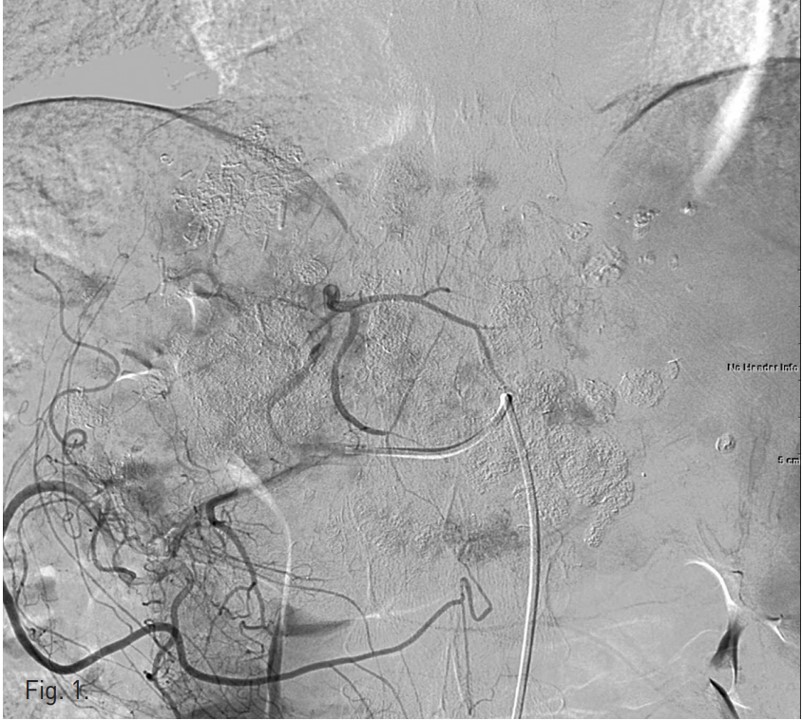

우측 대퇴동맥을 천자하여 복강동맥과 총간동맥 혈관조영술을 시행하였고 좌측 간동맥에서 혈류공급을 받는 다수의 과혈관성 종양이 관찰되었음(Fig. 1). 반복적인 TACE 후에도 CT영상에서 lipiodol defect area들이 보였기 때문에 간외측부순환에 의한 간세포암의 혈액공급 가능성이 있어 양측 횡경막하동맥과 내유방동맥 혈관조영술을 시행하였고 좌측 횡경막하동맥과 우측 내유방동맥에서 간세포암의 혈액공급이 관찰되었음(Figs. 2, 3). 이들 동맥의 혈관조영 영상에서 간정맥이나 폐혈관과의 shunt는 보이지 않았음. 2.0F 미세카테 타를 5F 카테타내 에 coaxial로 삽입하여 사용하는 동안 heparin mix 된 saline으로 카테타 flushing을 유지하였음. 각각의 간세포암 혈액 공급 혈관을 2.0F 미세카테타로 선택하여 lipiodol 13 ml와 adriamycin 60mg emulsk)n을 주입하였고,간외측부순환들은 추가적인 젤폼 색전술을 시행하였음. 색전술후 사진에서 종양내 lipiodol이 축적되고 과혈관성 종괴가 안 보이는 것을 확인한 후 시술을 마쳤음.

Fig. 1.

Fig. 1. Common hepatic arteriogram shows multiple hypervascular tumor stainings in the remnant left hepatic lobe.